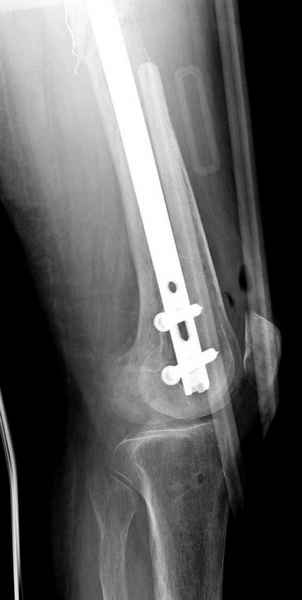

Для предупреждения кровотечения во время рассверливания, за день до операции провели эмболизацию сосудов питающий метастаз. http://radiology.rsnajnls.org/cgi/reprint/150/3/673.pdf (7-11, 12-15-16)

С минимальным рассверливанием и ретроградным методом провели остеосинтез бедра 12 мм гвоздем. (17-20)

Кровопотеря во время операции меньше 100 мл.